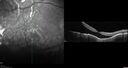

Macular fold - resolved with time70 x angesehen